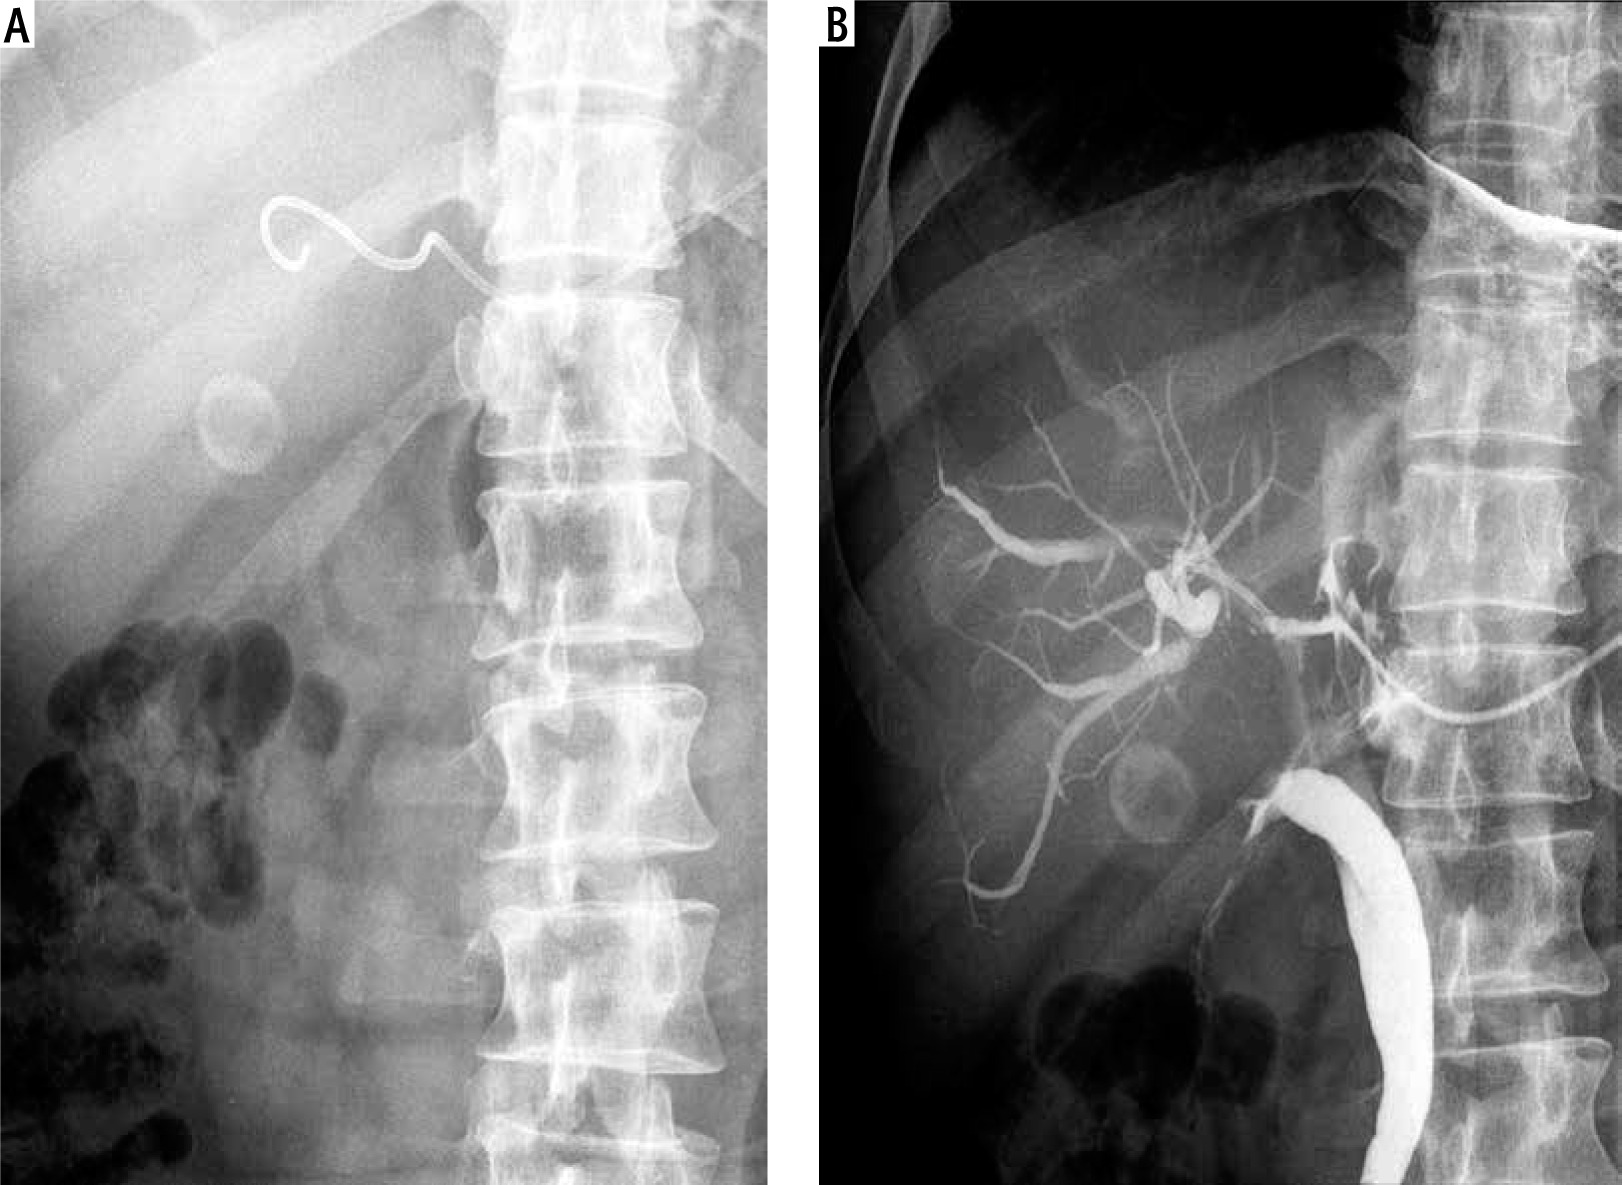

Fig. 1

Percutaneous transhepatic biliary drainage performed using an 8F catheter. A) 8F catheter introduced into the bile duct. B) Checking for catheter patency by injecting contrast through the catheter into bile ducts during follow-up cholangiography

Fig. 2

Percutaneous transhepatic biliary drainage performed using a 5F catheter. A) 5F catheter introduced into the bile duct. B) Checking for catheter patency by injecting contrast through the catheter into bile ducts during follow-up cholangiography

PTBD was performed under ultrasound guidance with careful localization of the biliary tree and proper selection of the entry site. The procedure was performed using local anaesthesia. No conscious sedation was applied. The route for BD depended on the location and available ‘window’ for optimal access to the biliary tree. The access site (right or left lobe puncture) was chosen according to the pre-procedural imaging. Generally, the most commonly used method was the trocar technique using an 8F multisidehole catheter (Boston Scientific, Boston, USA), guiding it into the bile duct (Fig. 1). If the introduction of an 8F catheter into the bile duct was difficult or impossible due to the position or the diameter of the bile duct, a modified trocar method using a multisidehole 5F catheter (Boston Scientific, Boston, USA) was used instead. With this technique, a 14 gauge needle was first introduced into the bile duct. Subsequently, a 5 F catheter was introduced through the needle into the bile duct. After introducing the catheter and the establishment of BD through the catheter, the needle was removed (Fig. 2). The catheter was then secured to the skin and connected to a bag attached to the skin for continuous PTBD. In cases which required introduction of more than one catheter in order to improve BD, additional catheters were introduced by the same method in other selected bile ducts. If a catheter problem occurred, it was resolved by repositioning and flushing of the catheter or by introducing a new one.

The number and size of the catheters were determined individually for each patient by the clinicians and interventional ultrasonographists. Their decisions were based upon clinical considerations, the size and location of the bile duct and its relationship to the surrounding vascular structures. Colour Doppler sonography was performed prior to intervention in order to determine the catheter pathway through the liver tissue towards the targeted bile duct, avoiding vascular structure damage. In general, colour Doppler sonography was not used during the intervention as it was more difficult to follow the catheter tip passing through the liver tissue. Adequate drainage is usually confirmed by a steady decline in serum bilirubin concentrations. Catheter patency was checked by injecting contrast and observing its passage through the catheter (Figs. 1, 2).